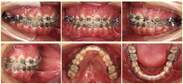

口内检查(图2):恒牙列;全牙列双侧磨牙近中关系,上中线左偏1mm,下中线右偏3mm,全牙列反合、牙弓中段开合5mm,上牙弓呈三角尖形12,25腭侧阻生,22缺失,左侧21、23牙槽突裂,软腭后壁部分缺如,无口鼻瘘;口腔卫生不佳